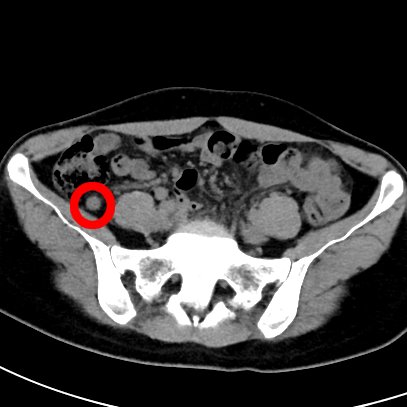

患者于3年前出现腹痛,以脐周及右下腹为主,疼痛反复发作,药物治疗后均无明显改善,辗转多家医院就诊,大大影响了患者的生活质量。近日患者来到我院脾胃肝胆科主任徐宏伟教授门诊就诊,徐宏伟主任结合患者的体征和CT检查结果,诊断为慢性阑尾炎。

术中利用无痛肠镜技术到达阑尾开口,采用最新的“eyeMAX洞察”子母镜系统直视下进入阑尾腔内,通过冲洗、引流、网篮套取等操作,将嵌顿于阑尾腔内的粪石取出,术后患者腹痛明显缓解,1h后即可下地行走。次日顺利出院。